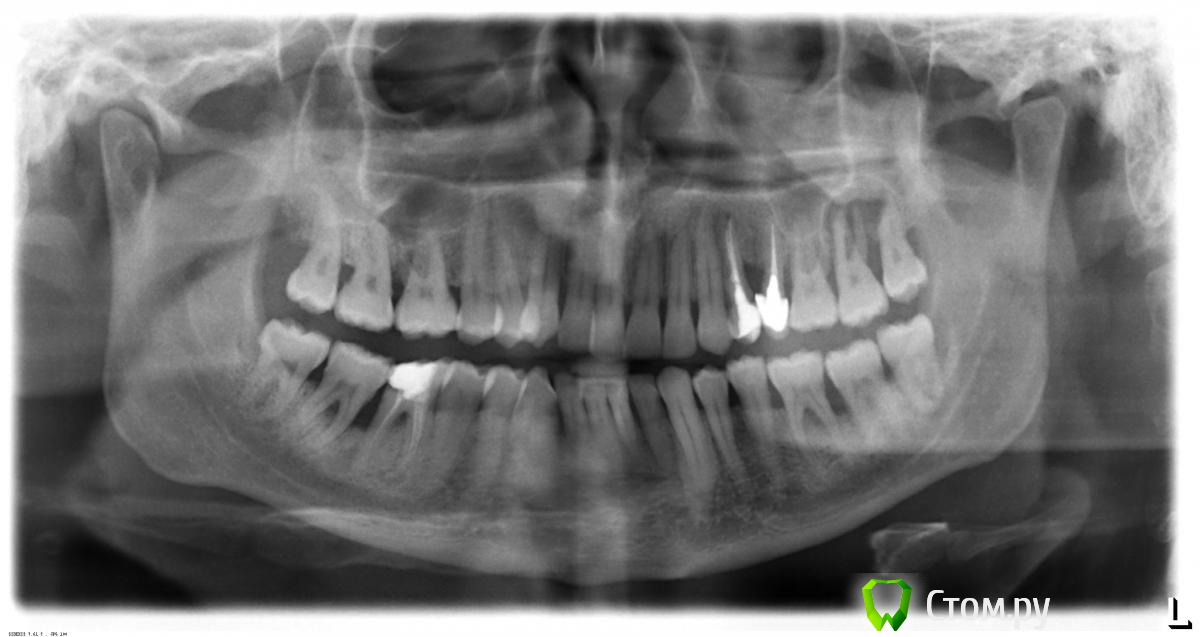

Макс111 Опубликовано 16 декабря, 2015 Поделиться Опубликовано 16 декабря, 2015 Добрый день!По возможности, прошу посмотреть мою КТ. Правда, не разобрался какую именно папку выкладывать, поэтомувот тут ссылка только на папку с файлами с расширением .DCM https://yadi.sk/d/NQrtBNRKmFtRC А вот тут на все содержимое диска вместе с программой для просмотра, на всякий случай:https://yadi.sk/d/O5yoL0QImFu3Y Так же к теме прикрепляю фото 24, 25 с внешней и внутренней стороны, а так же фото ниж ч там где 46 У меня пародонтит, и тд.В целом, вопрос по 24 и 25 зубу, между ними как видно большой карман. 25 это коронка на зубе, десна опустились и она полностью оголилась, видно уже корень , коронка на десной на пару мм. 24 это в общем то пломба огромная на весь зуб.Что можно сделать? Мне предлагают снять коронку, потом сделать лоскутную операцию, в ходе которой подсадить материал для формирования кости, чтоб уменьшить этот карман и потом сделать сделать коронку и на 25 и на 24 тоже коронку одеть.Какое ваше мнение по 24, 25? Как бы вы сделали, в какой очередности?27 и 28 потерял около 9 мес назад, над ними была киста, ее вырезали.А ну и плюс хронический гайморит. Так же прошу посмотреть в низу 46 зуб, можно ли туда вкрутить имплант или предварительно регенерировать кость нужно? каким методом?у 7 ки там такая форма, что между зубами видимо будет пустота? Как с этим бороться? Когда там был зуб так и были и поэтому 46 портился, стояла пломба, но 3 месяца назад он раскололся, сохранить возможности не было, плюс была киста и его пришлось удалить..Стоит ли сразу удалить 48, чтоб он не давил на 47 или можно подождать пока верх сделаю, чтоб было чем есть пока? Спасибо, если кто то посмотрит! Ссылка на комментарий

Макс111 Опубликовано 16 декабря, 2015 Автор Поделиться Опубликовано 16 декабря, 2015 вот такие прошлогодние есть Ссылка на комментарий